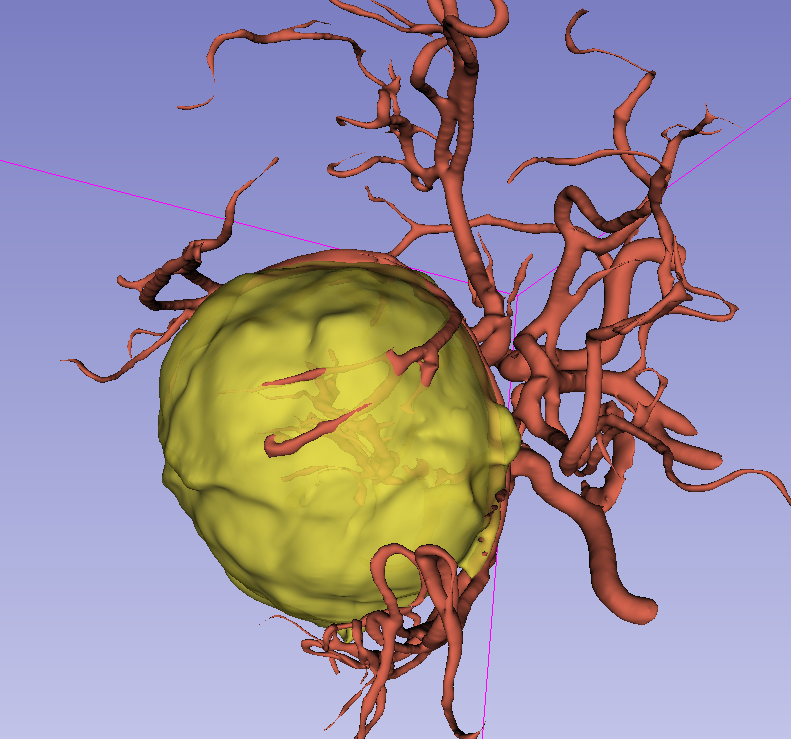

前颅窝底脑膜瘤常起源于前颅底筛骨筛板处的硬膜,瘤体多为双侧生长,少数为偏侧生长,女性稍多于男性。肿瘤可累及鸡冠和蝶骨平台的任何区域,是前颅窝肿瘤中最多见的一种。因为肿瘤位于前颅窝底,额叶在功能上属于“哑区”,患者就诊发现肿瘤时瘤体多已巨大。主要症状可有颅内压增高症状、视力减退、癫痫以及精神症状等。该患者主因“左眼失明10个月,头痛3个月”就诊。术中采用双额冠状开颅,左侧为主,由于肿瘤体积巨大,术中切除少许薄层额叶脑组织,边离断基底、边瘤内减压,分块切除肿瘤,最终探查肿瘤基底主要位于鸡冠、筛板、蝶骨平台、鞍结节、前床突处硬膜,术中见肿瘤供血主要来源于前颅窝底硬膜及大脑前动脉分支,术中仔细辨认供血动脉、过路血管,大脑前动脉及其分支保护完好,术中见视神经、视交叉受压明显,尤其是左侧视神经已缺血苍白,最终达Simpson II级切除。术者体会,该患者术前行多模态重建,可见瘤表数条粗大的静脉,术中切莫过早离断肿瘤的引流静脉,以防因引流不畅致瘤体肿胀出血;术前行多模态重建,利于鉴别供血动脉、过路血管,早期离断供血动脉更利于肿瘤切除;该类肿瘤基底一般较为广泛,不能盲目离断基底,尤其是近鞍结节处,可以于中线处离断基底,进入第一间隙后向两侧探查并保护视神经,待充分缩小瘤体看清楚毗邻的血管神经后再将其完全切除;术毕做好多层颅底重建以防脑脊液漏。另外,该患者术前左眼失明已达10个月,术后第1天即有光感,术后1月复查左眼视力可达50cm内数指,这在临床中非常少见,对于此类病人,不要轻易放弃挽救视力的任何机会。